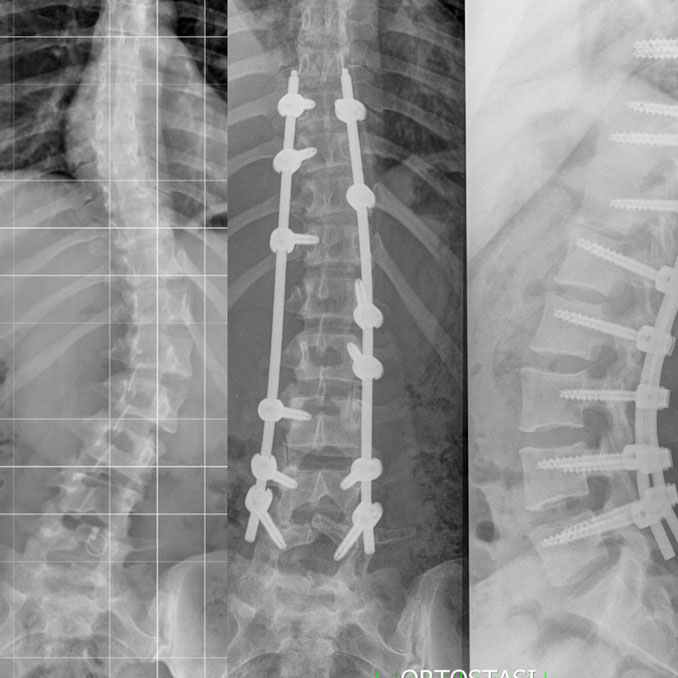

Uno degli interventi più comuni per trattare queste condizioni è l’artrodesi lombare o dorso-lombare, spesso accompagnata dall'uso di viti, barre e gabbie (cage). Molti pazienti chiedono se, dopo l'intervento, potranno tornare a fare una vita normale, inclusa la pratica di sport come il calcio.